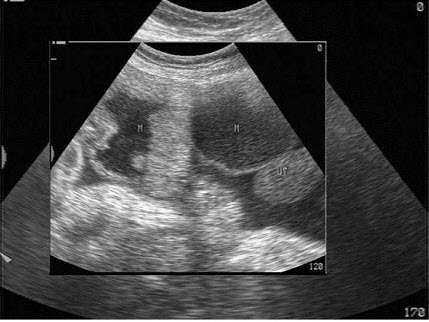

20、单项选择题

女,26岁,停经3个月,HCG阳性。根据B超检查声像图如下,最可能的诊断为()

A.葡萄胎

B.子宫肌瘤

C.稽留流产

D.不全流产

E.绒癌